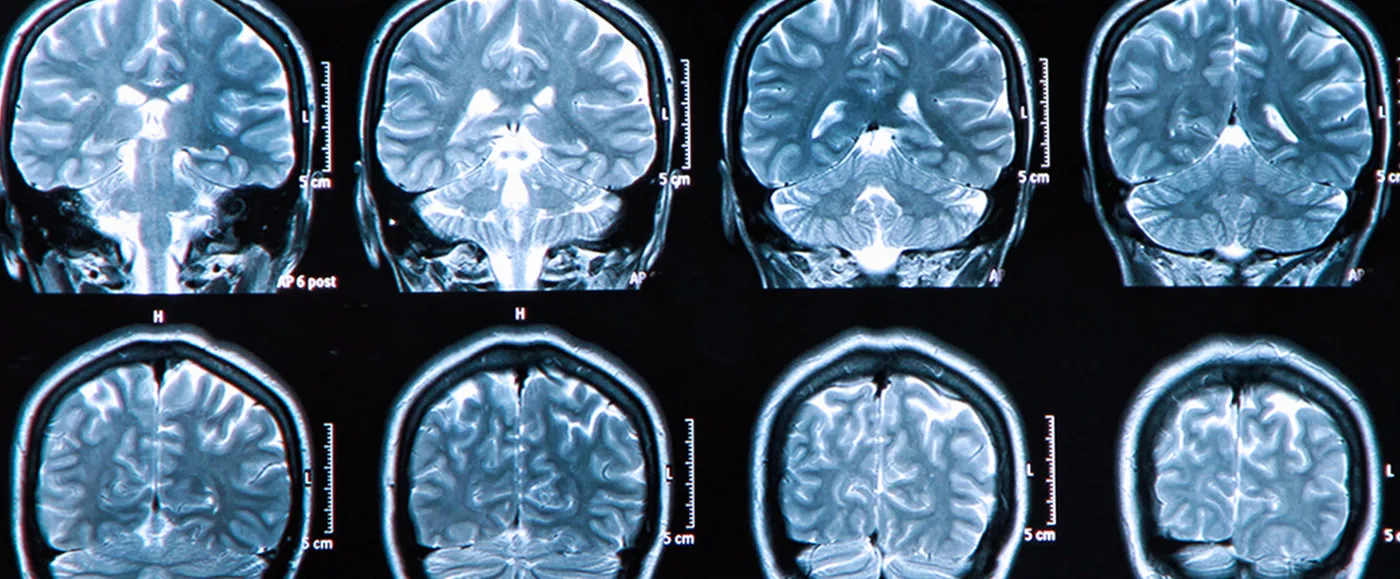

How is epilepsy diagnosed?

The diagnosis of epilepsy is based on a detailed description of the events experienced by the patient before, during and after a seizure. Electroencephalography and other investigational technologies can support the clinical diagnosis of epilepsy and help with the classification of partial-onset or generalized seizures1.